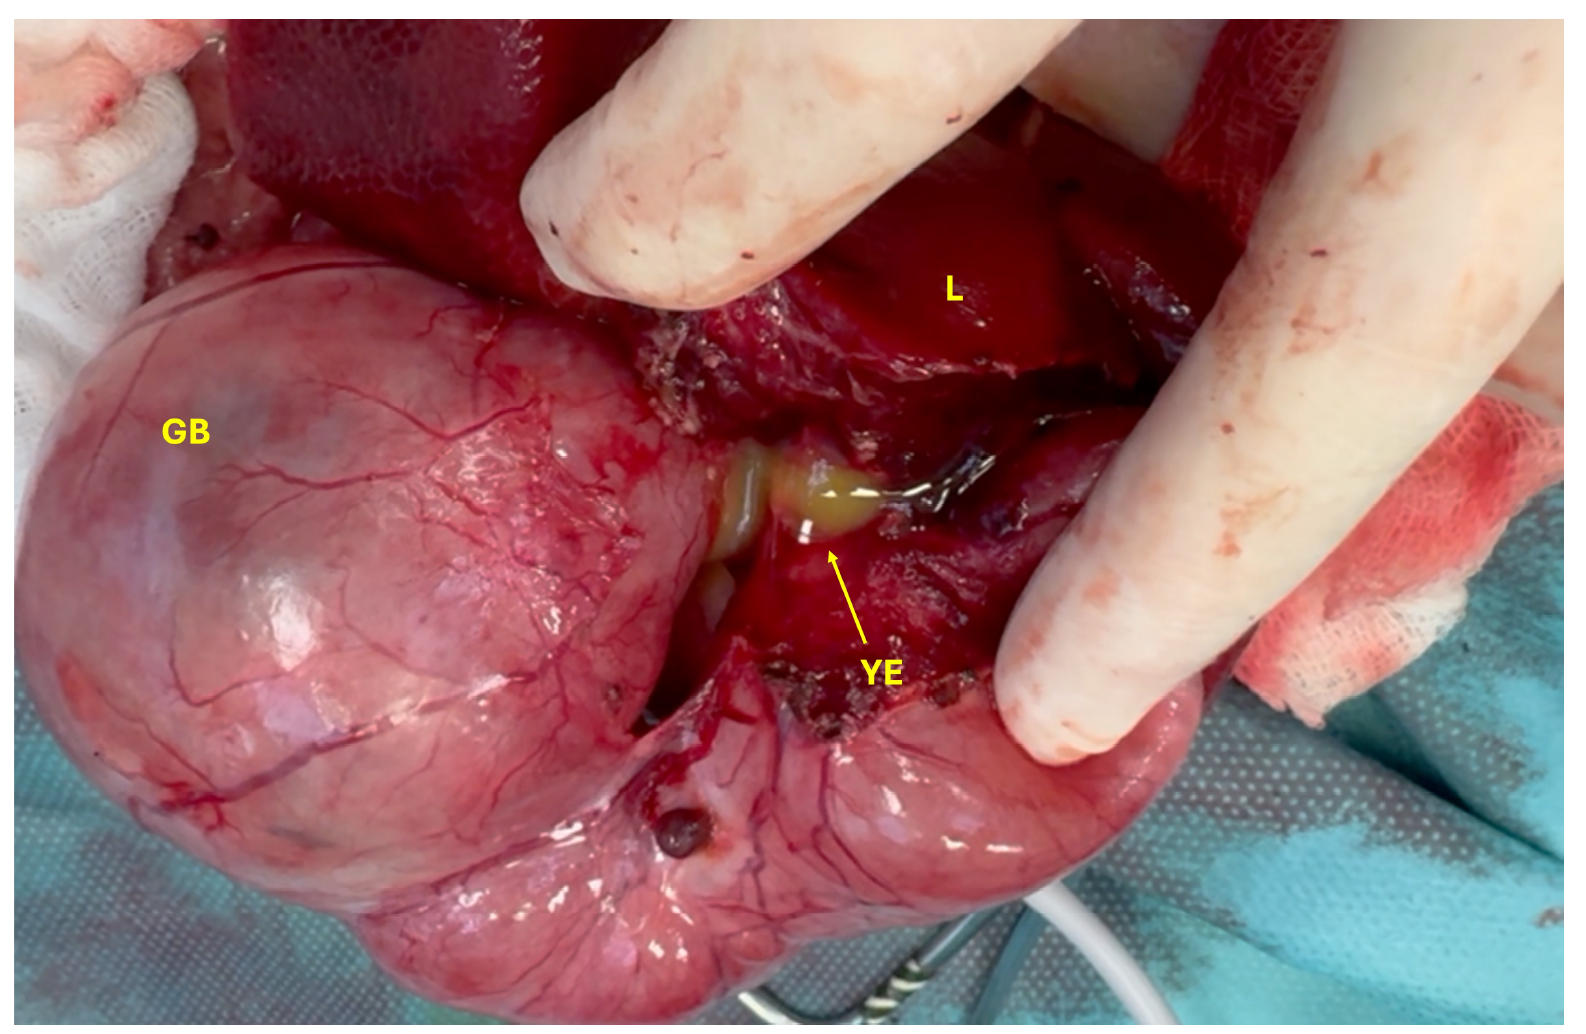

胆囊和胆总管内充满了黄色渗出物(脓液和胆汁的混合物),在开始解剖时,渗出物开始从肝脏漏出(下图)。胰腺右侧出现严重炎症,主胰管扩张,也含有黄色渗出物。胃部为空且受压,可能是由于扩张的胆囊和胆总管的压迫效应所致。

↑ 胆囊(GB)和肝脏(L)渗出的黄色渗出物(YE)。